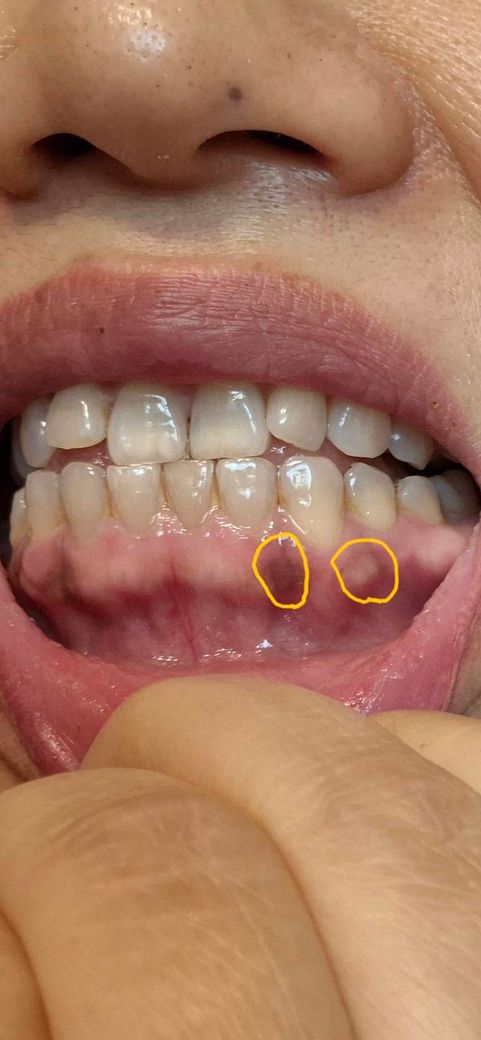

사진상 오른쪽 약간하얀 반점같은건 생긴지 1주일 가량 됐고 약간 통증이 있습니다

그리고 왼쪽 거무스름한것은 생긴지 좀 됐는데 통증은 없습니다

검은색으로 보이는 부분은 잇몸에 멜라닌 착색 등으로 인해서 어둡게 보이는 것입니다. 문제가 되는 것은 아니기 때문에 걱정하지 않으셔도 됩니다. 그 외에 다른 부분도 정상적인 잇몸의 상태이기 때문에 크게 걱정하실 필요는 없을 것으로 생각됩니다.